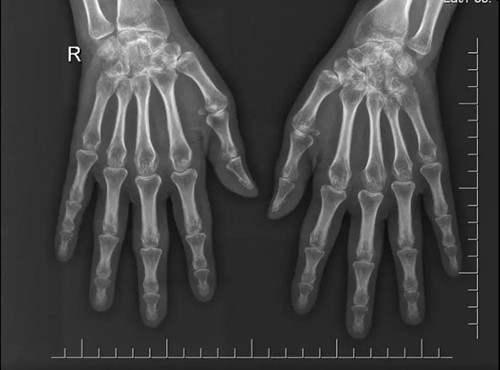

患者為44歲中國女性,10個月前開始出現多關節腫痛。查體可見患者右手近端和遠端指間關節外形呈梭形腫脹,有壓痛,雙腕關節及膝關節腫脹、壓痛,晨僵時間>30min,X線片(見圖1)示雙側手腕關節、指間關節間隙縮小。

圖1 患者雙手X線片